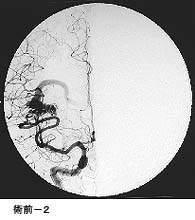

破裂脳動脈瘤に対するGDC(コイル)塞栓術

術後 コイルにより動脈瘤が写らなくなりました。